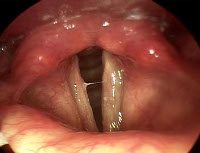

Во время ларингоскопии у пациентов с реальным крупом выявляются катаральные изменения в слизистой оболочке гортани (отек и гиперемия), сужение просвета и характерная бляшка дифтерии. При осмотре горла часто возникают приступы дифтерии. Они плохо удаляются и часто выявляют небольшие язвенные дефекты снизу. В случае ложного крупа ларингоскопия определяет катаральное воспаление, сужение гортани и накопление в ней большого количества густой слизи. Возможна легко снимаемая доска. Бактериологическое исследование мазков из горла помогает полностью различить истинные и ложные задние конечности. Обнаружение 100% вacillus вacillus подтверждает диагноз реального крупа.

Круп может быть диагностирован педиатром, терапевтом или отоларингологом. При развитии осложнений бронхолегочной инфекции необходима консультация пульмонолога. Круп при сифилисе диагностируется вместе с венерологом, с туберкулезом гортани - вместе с врачом по туберкулезу. Групповая диагностика учитывает характерные данные клиники, анамнеза, данные аускультации, ларингоскопию и дополнительные анализы.Сухой хрипящий звук слышен в легких во время аускультации. Появление влажных ресниц свидетельствует об обострении заболевания. Ларингоскопическое изображение позволяет определить степень сужения гортани и частоту процесса, выявить волокнистые пленки, характерные для дифтерии. Патоген проверяется с помощью микроскопии и бактериальной культуры мазков из зева, ПЦР, ИФА и диагностики РИФ. Для выявления сифилиса обязательным является тест RPR. Степень гипоксии оценивают на основании анализа газообразного состава крови и ее кислотно-основного состояния.